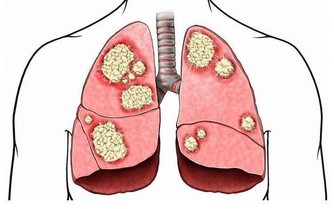

1“臭”

嘴裡、呼出的氣體有尿臭味

口臭是常見的現象,但如果這種臭是尿臭味,那說明腎可能出大事了。

腎病進展到慢性腎功能衰竭階段(俗稱尿毒症)時,患者口中、呼出的氣體中常帶有尿味。

這是因為,此時尿素無法被正常代謝,瀦留體內,導致呼吸散發出尿味。